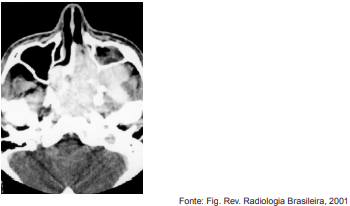

Adolescente, sexo masculino, 15 anos, iniciou com obstrução nasal unilateral e episódios de sangramento recorrentes de fossa nasal esquerda, em média, três vezes por semana. Submetido a exame tomográfico que evidenciou uma massa na nasofaringe com alargamento da fossa pterigopalatina à esquerda.

Analise a imagem abaixo.

Sobre o diagnóstico dessa doença, baseado na clínica e na alteração tomográfica, é correto afirmar que o/a